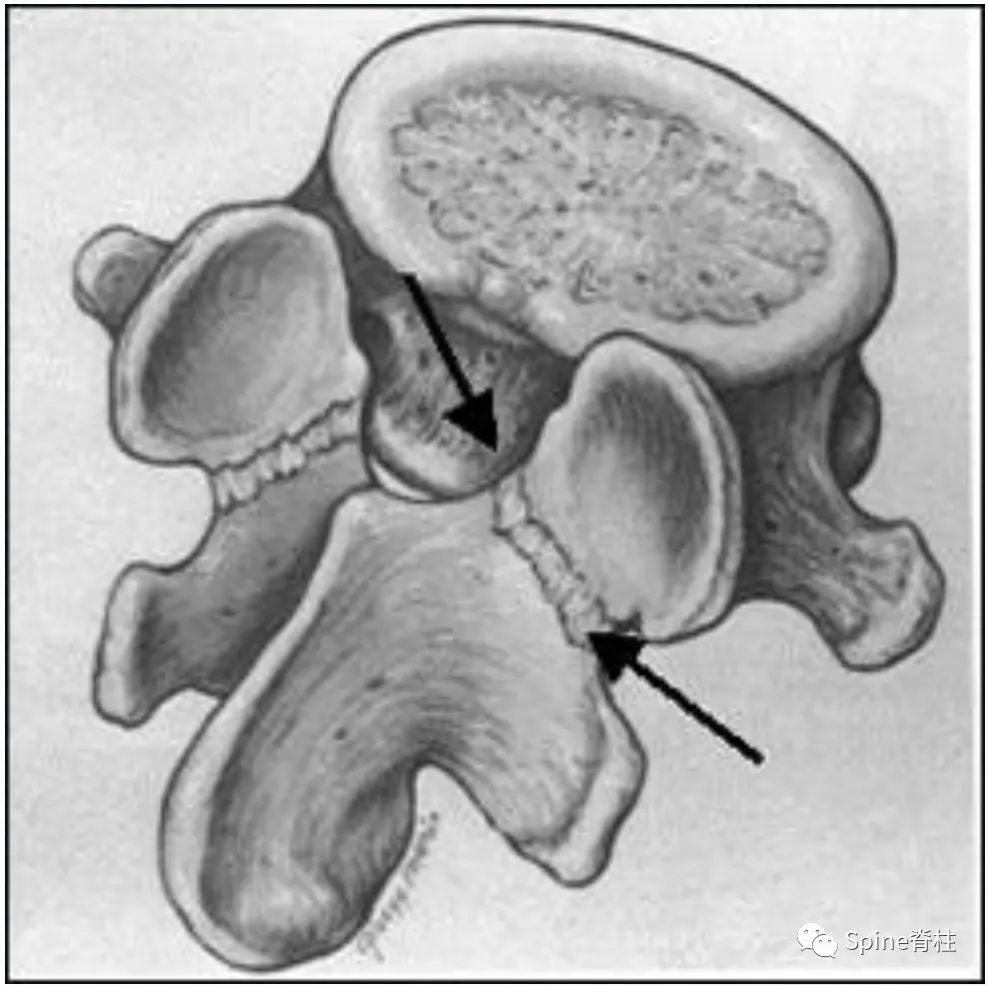

L5脊椎骨背面斜位示意图。显示椎弓的各部分:阴影区1=峡部,2=椎板,3=椎弓根。虚线处为峡部裂的常见部位。

枢椎(C2)的侧面观示意图。上下关节突的偏移关系使峡部(阴影区)被拉长。虚线显示了上颈椎过伸性损伤时枢椎最常见的受损部位 (hangman骨折)。